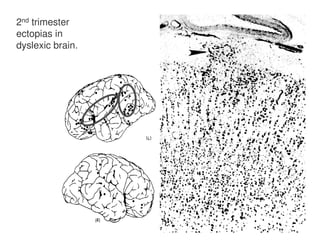

2nd trimester

ectopias in

dyslexic brain.

C6 KIAA 0319 controls neuronal migration during

early brain development in utero. Downregulation in

dyslexics may explain ectopias and other

mismigrations of magnocellular neurones